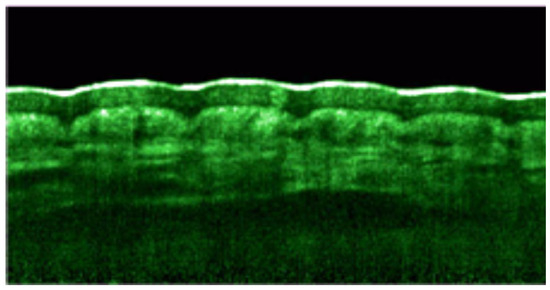

9. Optical Coherence Tomography